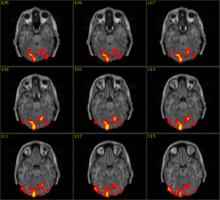

統計參數映射(SPM)和fMRI獲取方法的研究推動了事件相關fMRI的發展。事件相關fMRI是研究對單一事件的局部腦血流動力學反應。事件和一定的規則相結合,觀察在不同時間段對應不同事件的皮層區域的情況。此外,fMRI的非介入性質使它可作為一種理想手段來研究未知事件,即受試者只有在事件發生時才產生反應信號。圖3所示為光刺激事件的fMRI圖像。

也可研究正常人在MRI磁體中做夢的情況。雖然這些研究的實驗時間較長,但是相當有價值。處理事件相關的fMRI的統計工具(例如SPM)在這些研究中被廣泛使用。